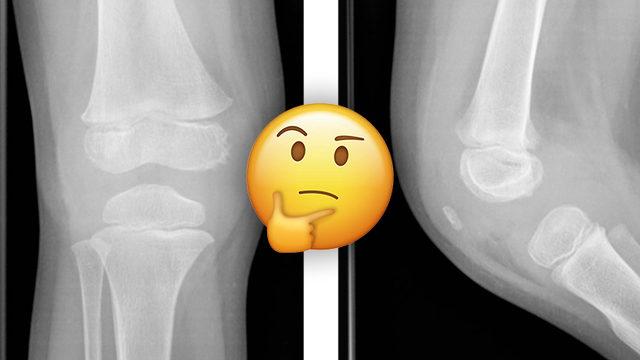

İskeletimiz, her 10 yılda bir kendini yeniliyor.

İnsan iskeleti, “modelleme” adı verilen bir süreçte oluşuyor ve yetişkin olana kadar büyüyor. Daha sonra yaklaşık her 10 yılda bir kendini tamamen yeniliyor. Kemik dokusunun ise yaklaşık %20'si, her yıl “yeniden yapılanma” yoluyla değiştiriliyor.